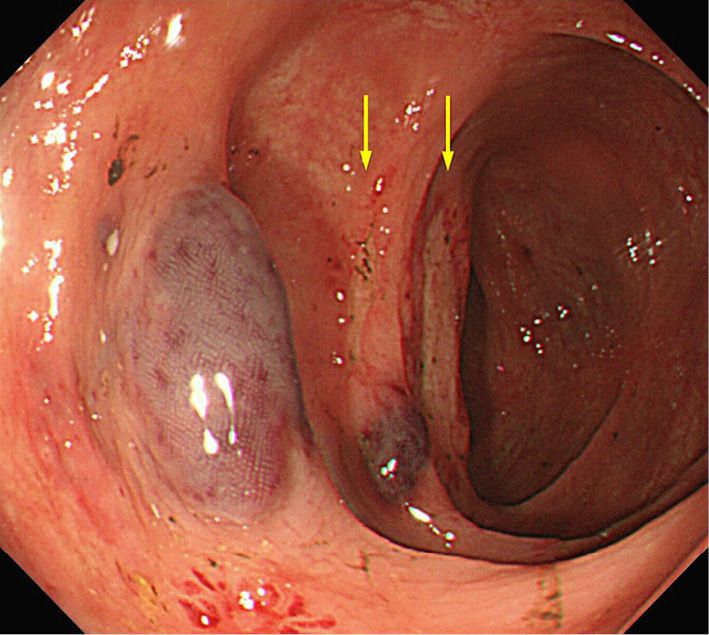

Рисунок 4. AL-амилоидоз у 80-летнего мужчины, повторная колоноскопия [17].

Повторная колоноскопия, проведенная через неделю после прекращения антикоагулянтной терапии, показала более мелкие и плоские подслизистые гематомы и развитие неглубоких язв (желтые стрелки).